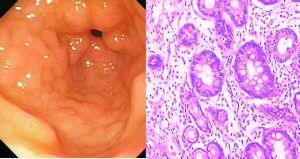

病理改變

1,胃鏡檢查主要有以下特點:①黏膜皺襞粗大加深變寬,呈腦回狀;②黏膜皺襞上可見橫裂,有多數疣狀隆起的小結;③黏膜隆起的頂端常伴有糜爛。2,鏡下觀:腺體肥大增生,腺管延長,有時增生的腺體可穿過黏膜肌層。黏膜表面粘液分泌細胞數量增多,分泌增多。黏膜固有層炎性細胞浸潤不顯著。患者常有胃酸低下及因丟失大量含蛋白的胃液引起的低蛋白血症。